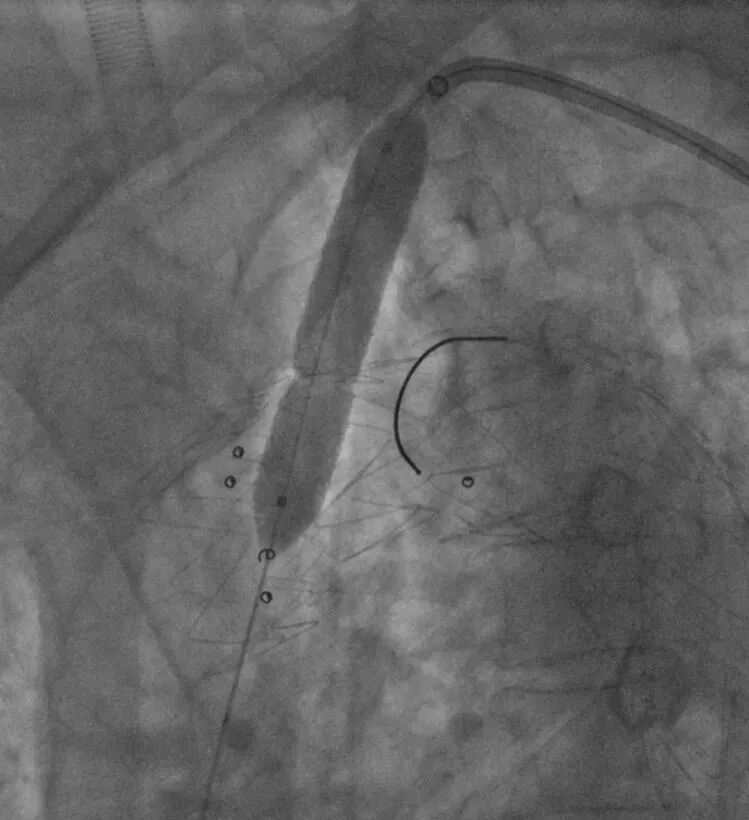

5. 左锁骨下动脉造影示:左锁骨下动脉少量造影剂外漏,根据术前计划,置入12-58mm LifeStream球扩覆膜支架,短肩球囊设计,避免导丝缠绕,顺利通过病变,并扩张释放。

导入LifeStream支架

球扩LifeStream支架

6. 最后造影效果满意,胸主动脉支架位置良好,血流通畅,无明显内漏,弓上三分支血供良好,左锁骨下动脉正向血流、双侧颈动脉和椎动脉显影好,颅内动脉显影好。

LAO术后造影

RAO术后造影